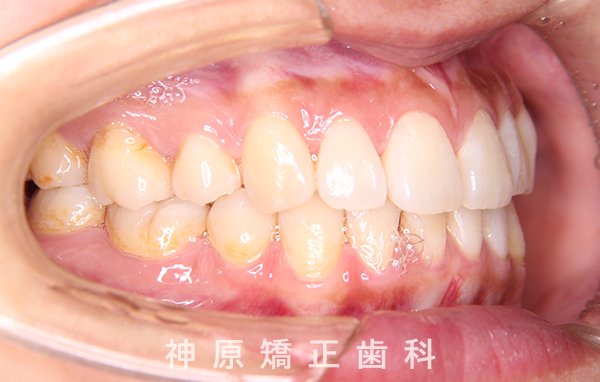

治療終了

治療前と治療後